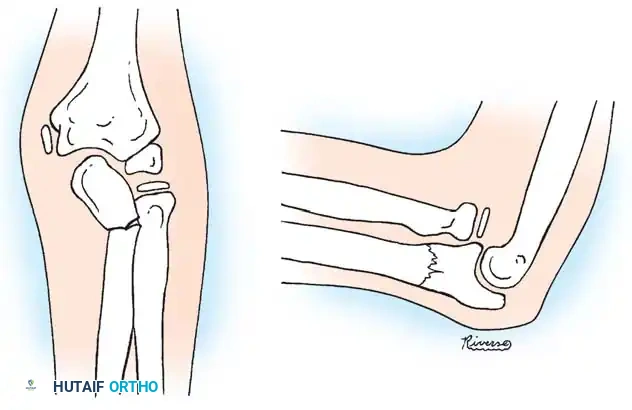

Physeal Injuries and Growth Arrest

In addition to metaphyseal both-bone fractures, physeal fractures of the distal radius and ulna are frequently encountered. Salter-Harris type I and II fractures are the most common; types III and IV are exceedingly rare.

While these physeal injuries typically respond well to closed reduction and casting, complications can arise. Lee et al. reported cases of premature closure of the distal radial physis following either severe physeal compression injuries (Salter-Harris type V) or repeated, forceful attempts at closed reduction.

Surgical Warning: Repeated manipulation of a pediatric distal radius fracture significantly increases the risk of iatrogenic physeal damage. If the initial reduction achieves greater than 50% apposition with acceptable alignment, further forceful attempts at perfect anatomical reduction should be strictly avoided.

Zehntner et al. described growth disturbances caused by partial closure of the distal radial physis, leading to a pseudo-Madelung deformity. This tethering effect results in ulnar deviation of the radius and relative ulnar overgrowth.

Image

Management of these growth arrests depends on the patient's age and remaining growth potential:

* Ulnar Shortening Osteotomy: For relative ulnar overgrowth.

* Opening Wedge Radial Osteotomy: To correct the articular inclination of the radius.

* Sauvé-Kapandji Procedure: A salvage option for severe distal radioulnar joint (DRUJ) incongruity.

* Epiphysiodesis: Of the contralateral or adjacent physis to prevent progressive deformity.